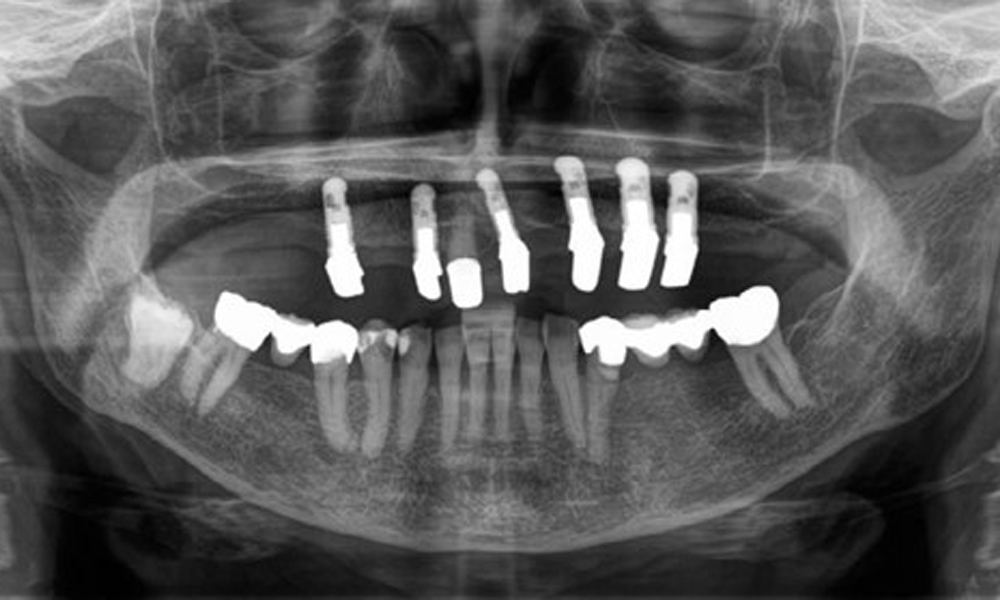

Radiologischer Befund

Aus dem radiologischen Befund zeigt sich ein teilbezahntes Gebiss mit Implantaten im Oberkiefer an 15, 13, 21, 23, 24, 25 und einer Teleskopkrone 11. Im Unterkiefer sind suffiziente Brücken von 37–34 und 45–47 vorhanden. 48 ist retiniert. 43 distal besteht der Verdacht auf Sekundärkaries und 44 mesial Verdacht auf Sekundärkaries. 44 ist mit einer nicht röntgenopaken Unterfüllung versorgt.

Es zeigt sich ein generalisierter horizontaler Knochenabbau von ca. 10–30 % und lokalisiertem vertikalen Knochenverlust an 22 und 42. (Abb. 5)